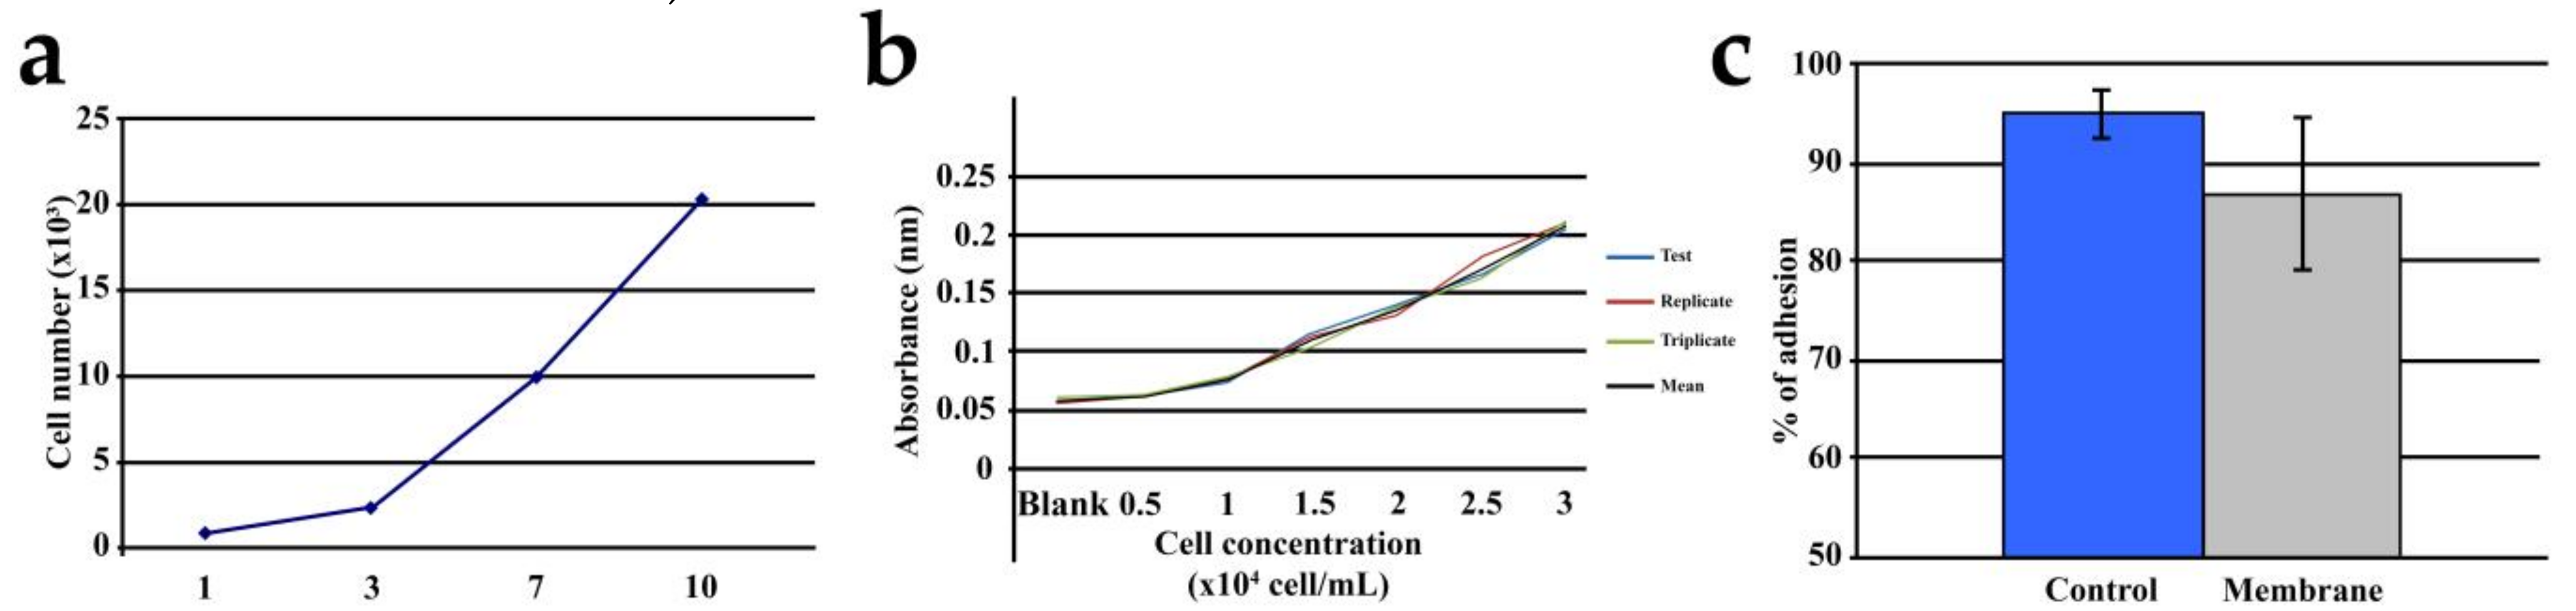

3.1. Cell Adhesion and Proliferation

3.2. Echocardiographic Findings